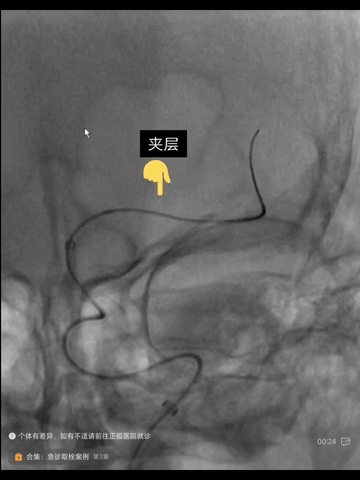

造影示下干恢复血流,其起始部狭窄亦明显改善,但左MCA主干出现一明显夹层